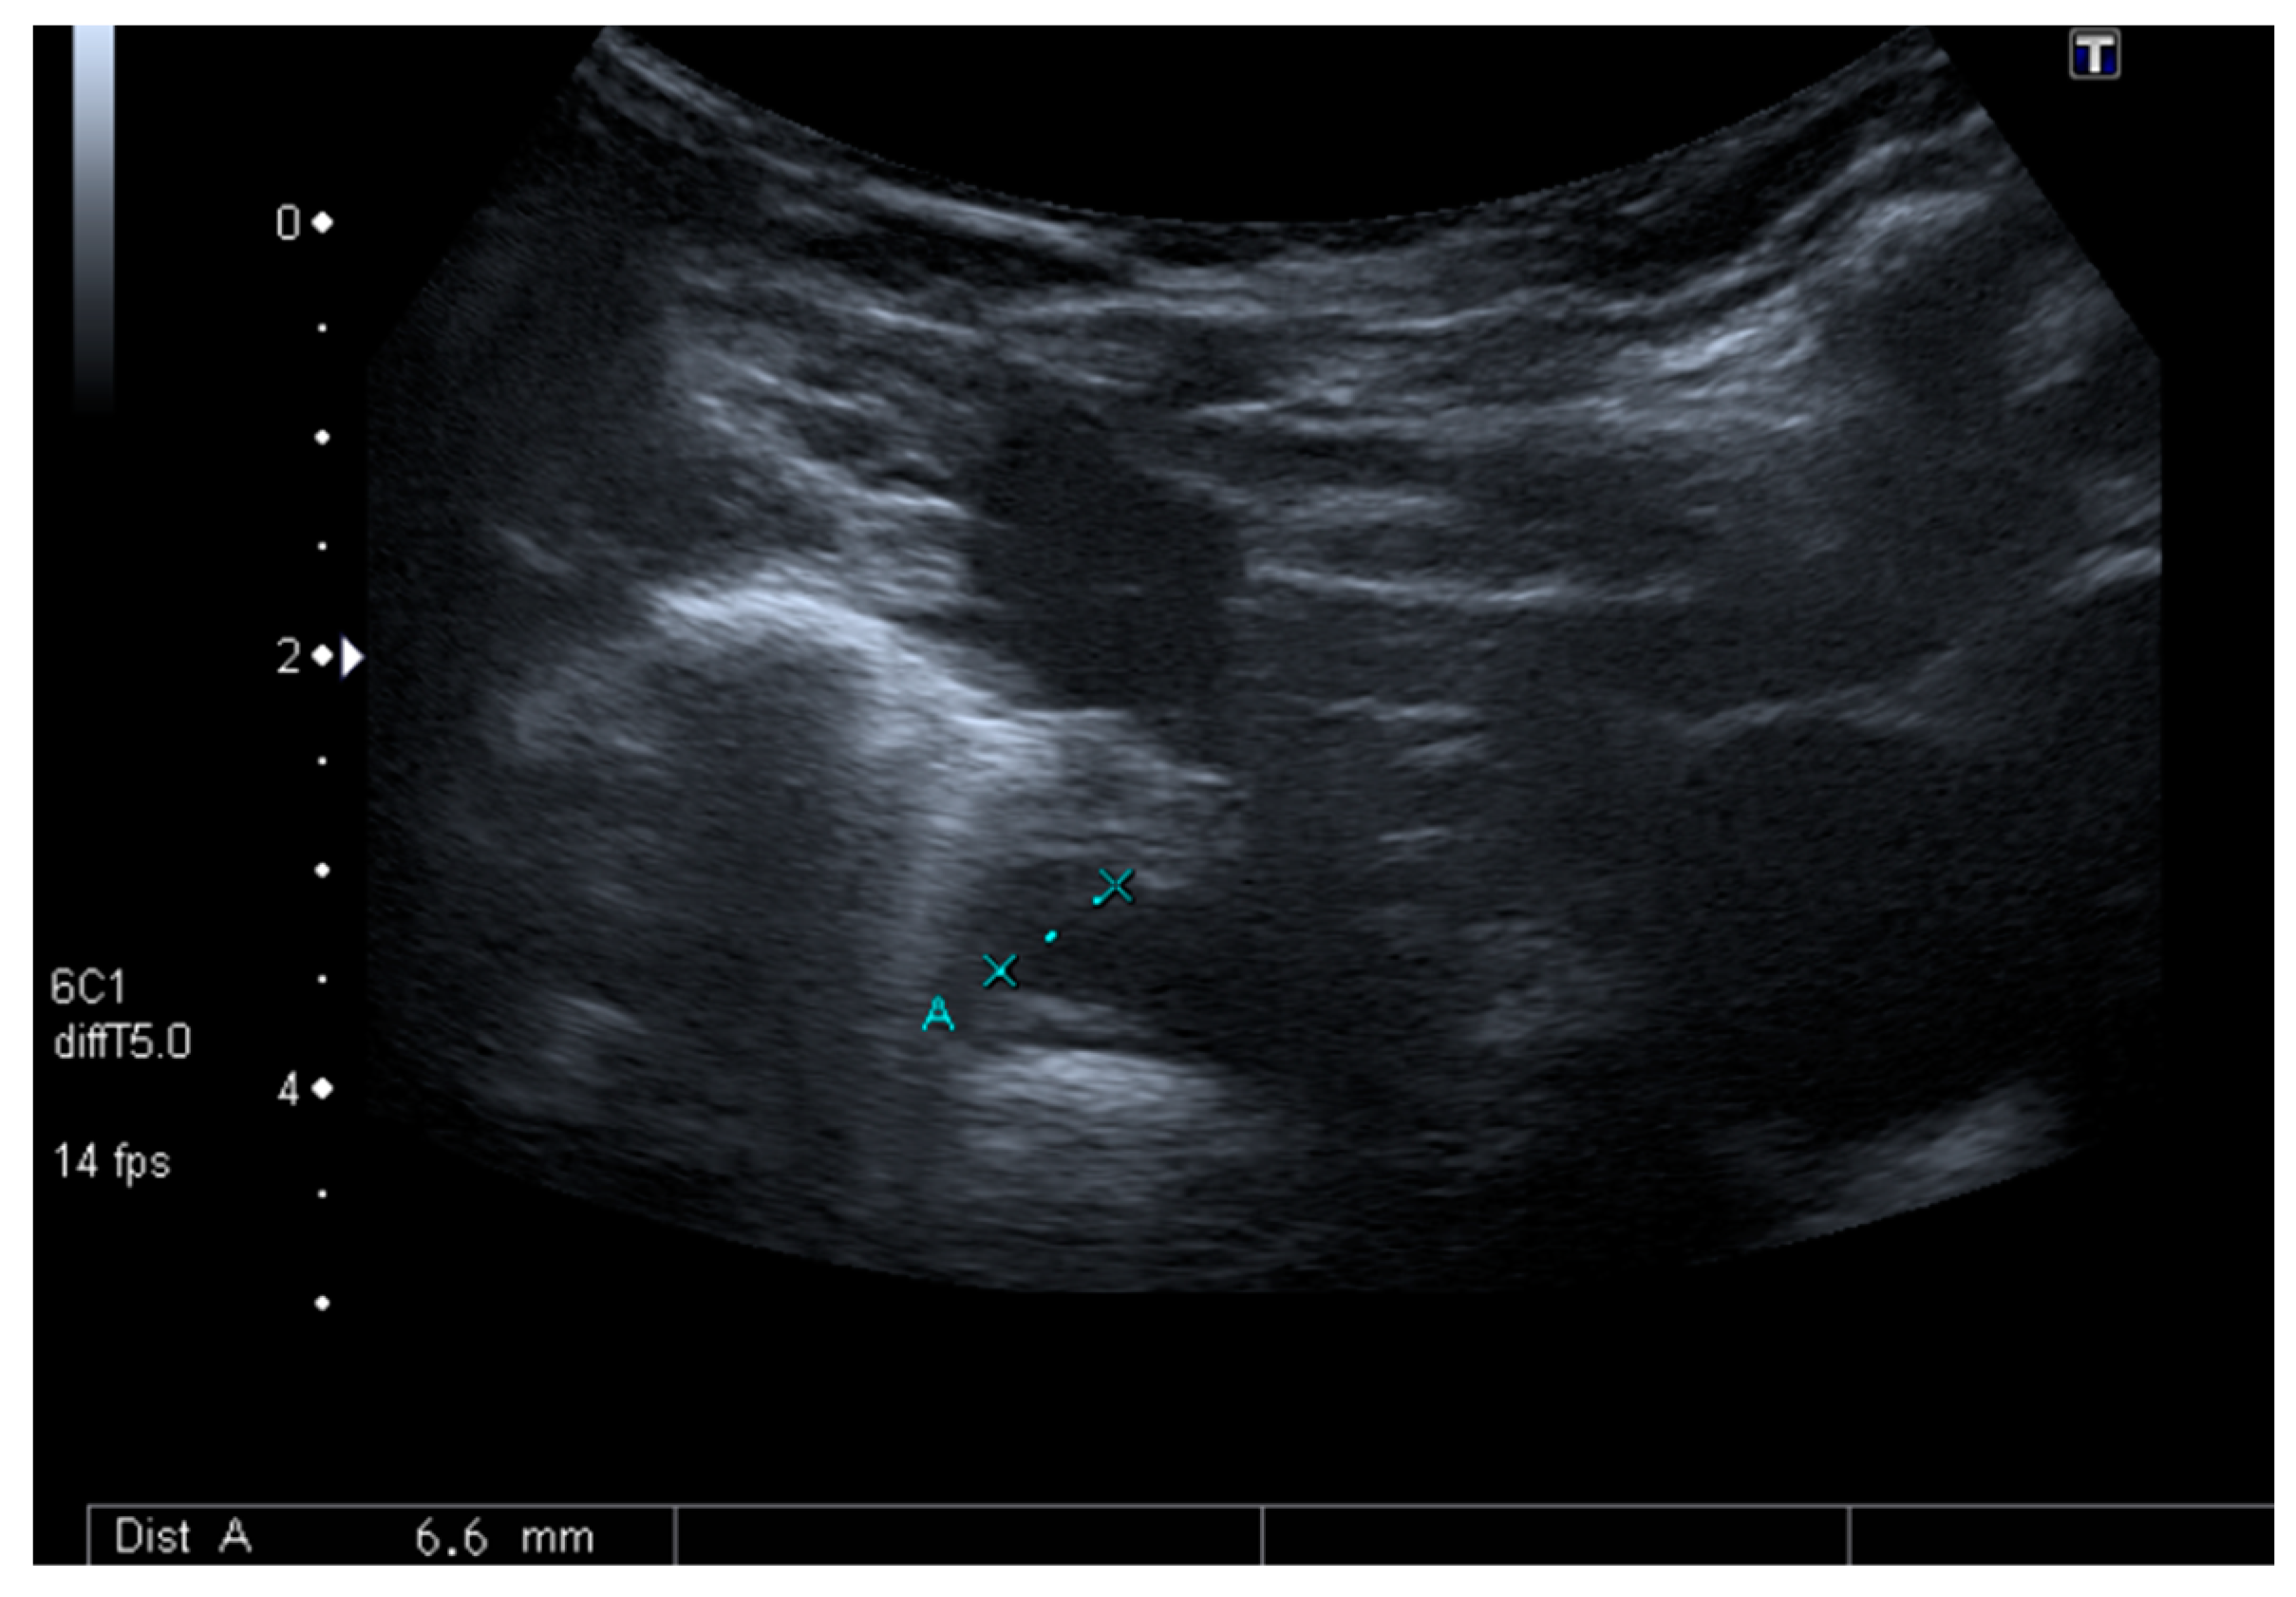

Although surgical drainage was considered, a follow-up CT scan showed a sustained decrease of the mediastinal lesions with antibiotics only. For this reason, the child was maintained under close surveillance with serial US (Figure 3). She maintained fever until the 6th day of antibiotics, after which a sustained clinical and laboratorial improvement was achieved. At the end of 4 weeks of IV antibiotics, the child was discharged without any symptoms and with complete resolution of the mediastinal lesions.

Lastly, existing literature from adult and pediatric patients highlights the importance of a prompt drainage. However, by the time we made the diagnosis, on day 4, there was no cervical collection and the mediastinal lesions were resolving, along with a sustained clinical and laboratorial improvement. The decision for a watchful waiting approach turned out to be successful. Since US was easily available and proved accurate, without having to subject the child to more radiation, we decided to use it to closely monitor the mediastinal lesions.

The authors thereby emphasize that, although CT scan is the gold standard for the diagnosis and control of acute mediastinitis, US imaging must be considered as an alternative radiological tool, reducing radiation exposure, whilst allowing clinicians to avoid surgical drainage in selected stable cases.

Figure 3. Follow up mediastinal ultrasound.